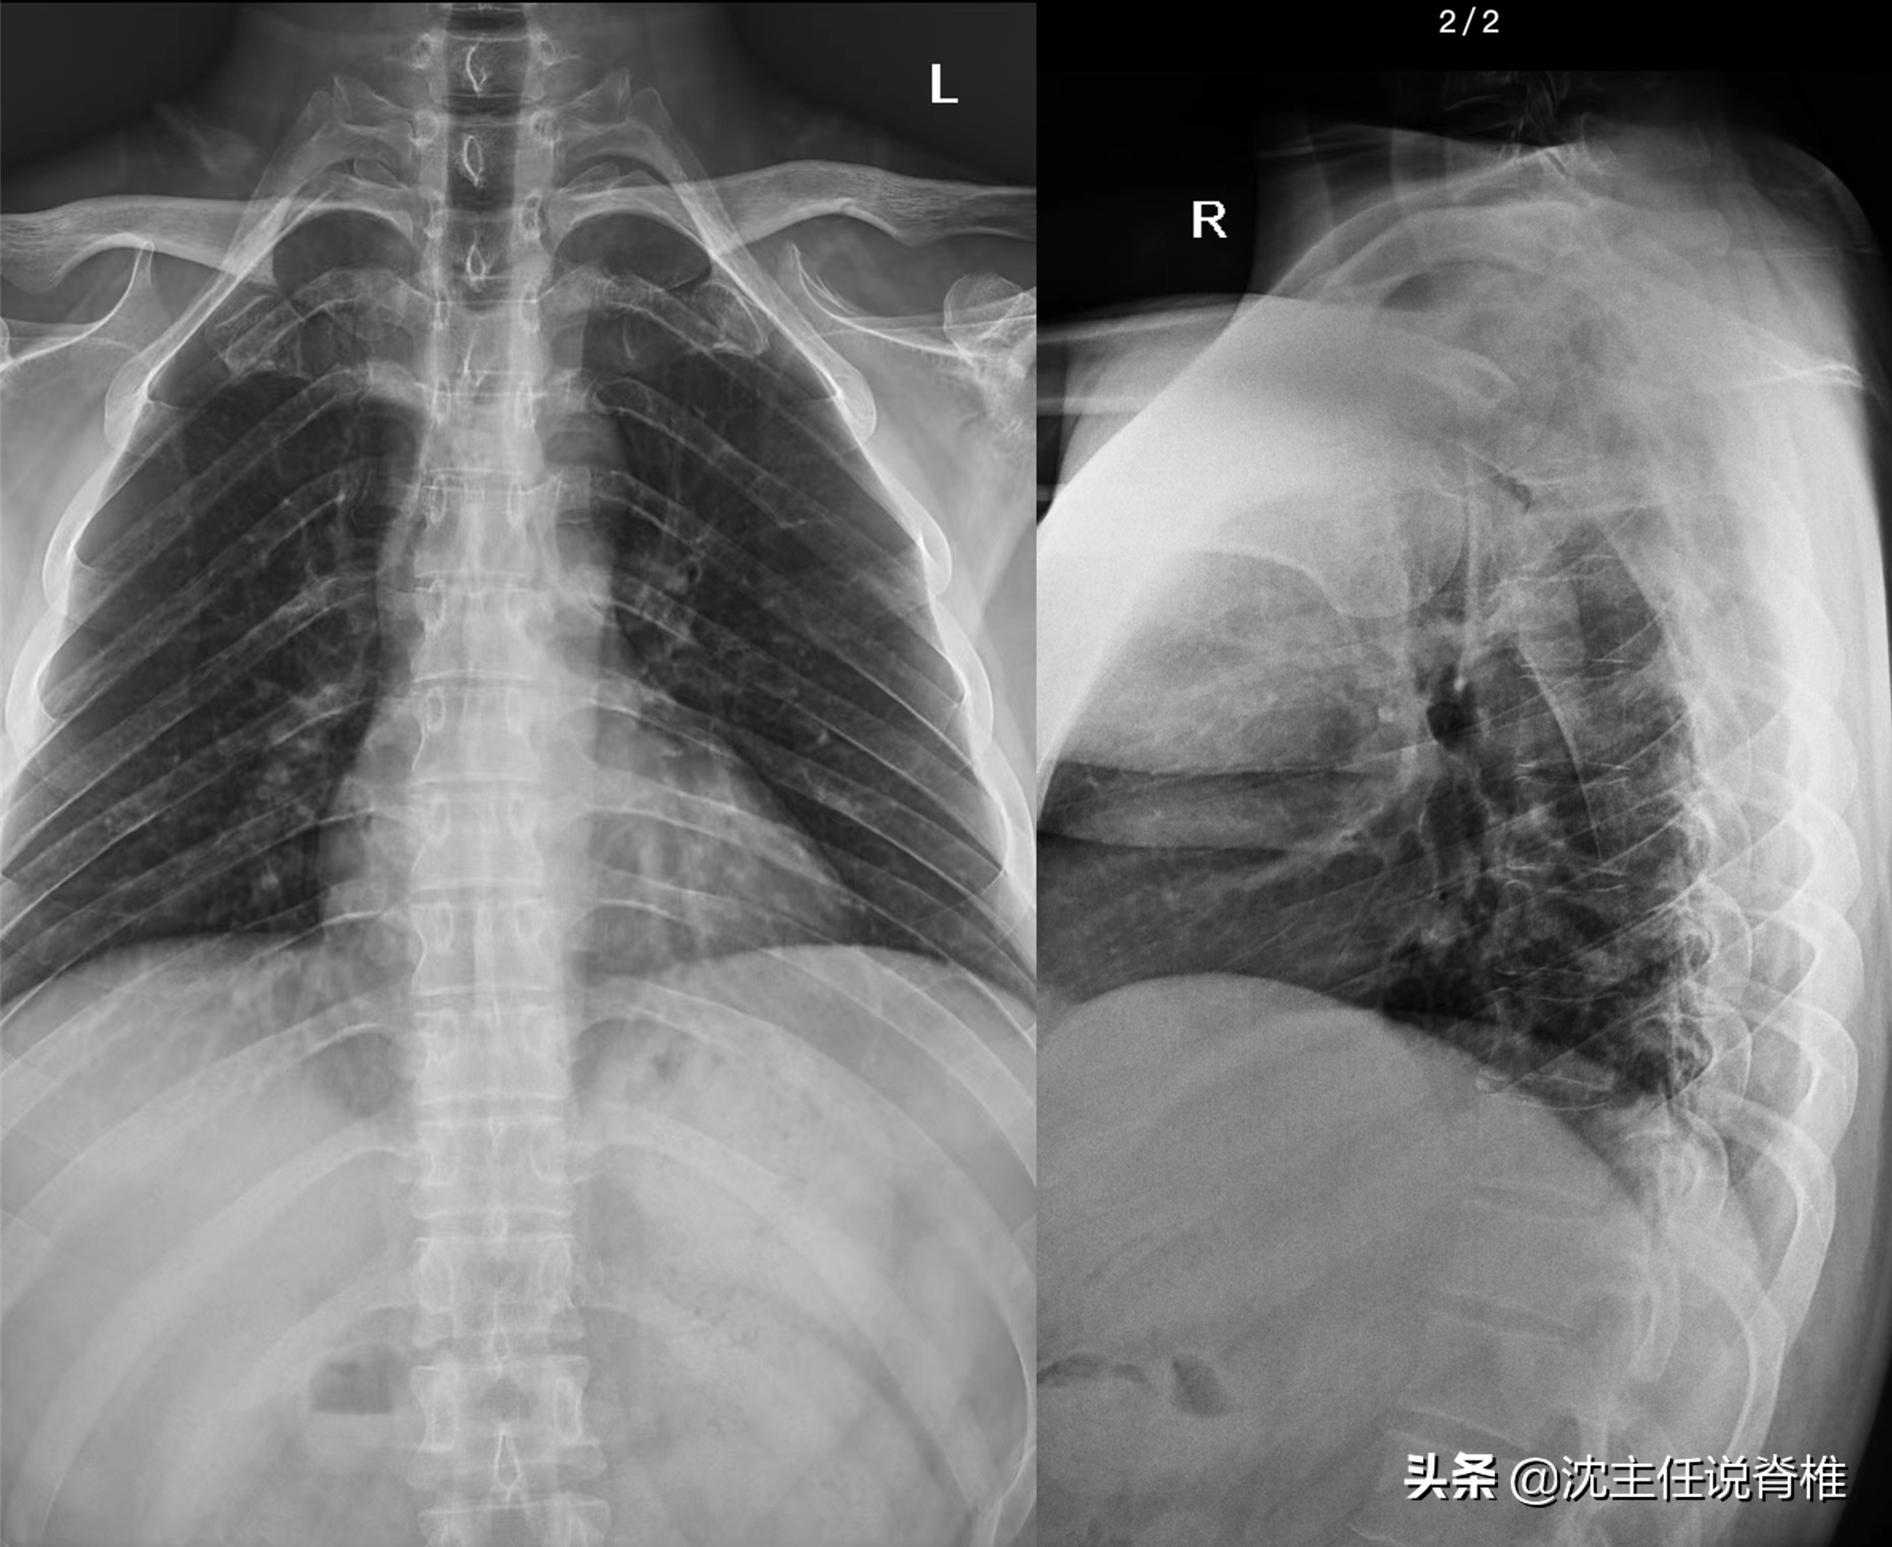

体格检查:右侧前中斜角肌紧张压痛,胸椎T4-5右压痛。胸椎X光检查:胸椎生理曲度存在,胸椎小关节不稳。